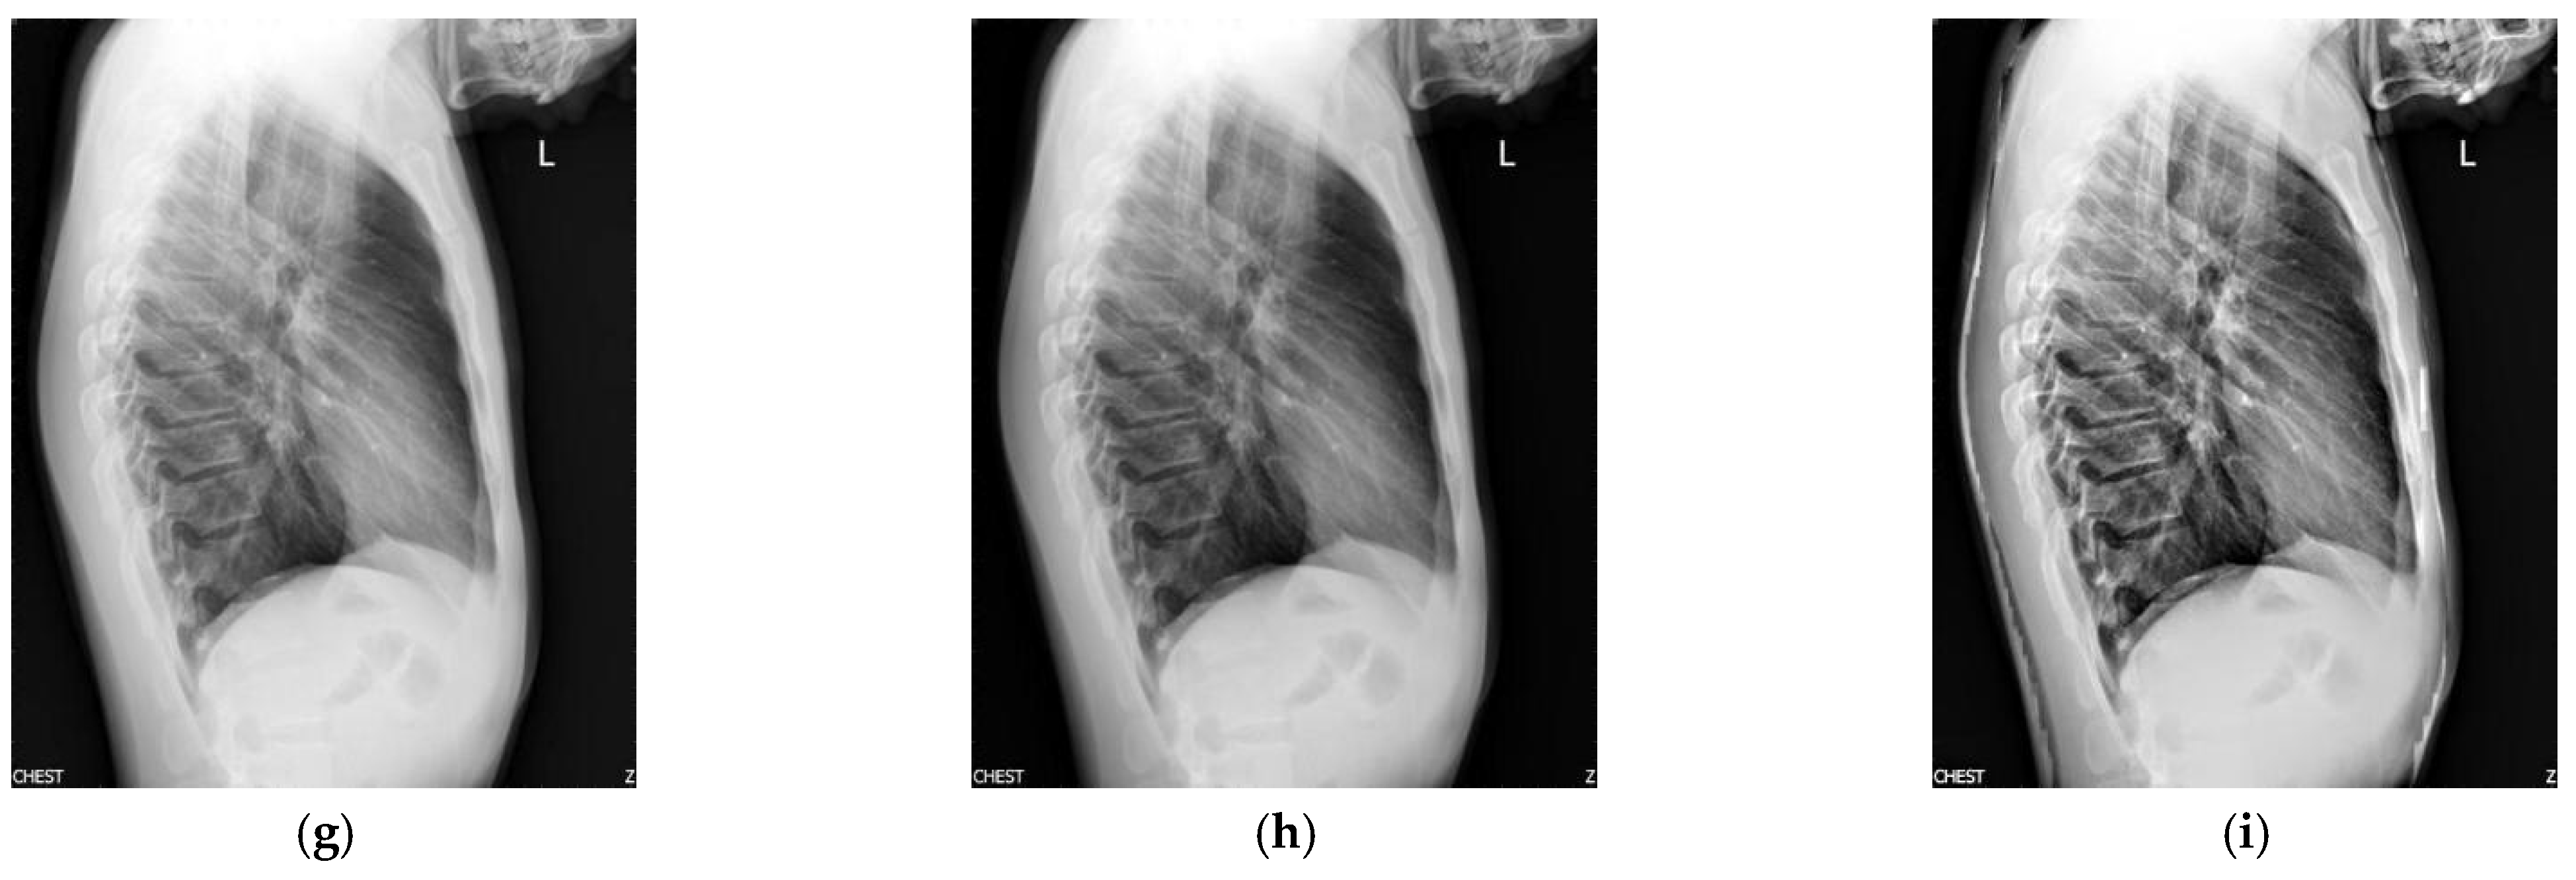

Figure 2 shows the enhancement images of eight approaches experimented on X-ray image 2. Figure 2a shows the original X-ray image 2; Figure 2b is the result obtained by McCann—the contrast is low; Figure 2c presents the image enhanced by RLBHE—it does not achieve the effect of image enhancement, the image is too dark, and we can hardly get effective information from it; Figure 2d shows the result achieved by RESIHE—the effect of enhancement is not obvious; the images obtained by TBCSSR and FuzzyII are shown in Figure 2e and Figure 2h, respectively. The contrast and the definition are low; Figure 2f and Figure 2g show the results enhanced by GDGIF and SMIPC, respectively. The two images appear to have noise amplification. The result enhanced by the proposed algorithm is shown in Figure 2i—it reveals more image details and suppresses the noise. Bone information can be clearly obtained, which is helpful for doctors to diagnose. Table 2 is the evaluation index values of various methods in Figure 2. Except for H, our method is the best for other indicators.

Figure 2.

Comparison on X-ray image 2. (a) Original image; (b) McCann; (c) RLBHE; (d) RESIHE; (e) TBCSSR; (f) GDGIF; (g) SMIPC; (h) FuzzyII; (i) Proposed method.